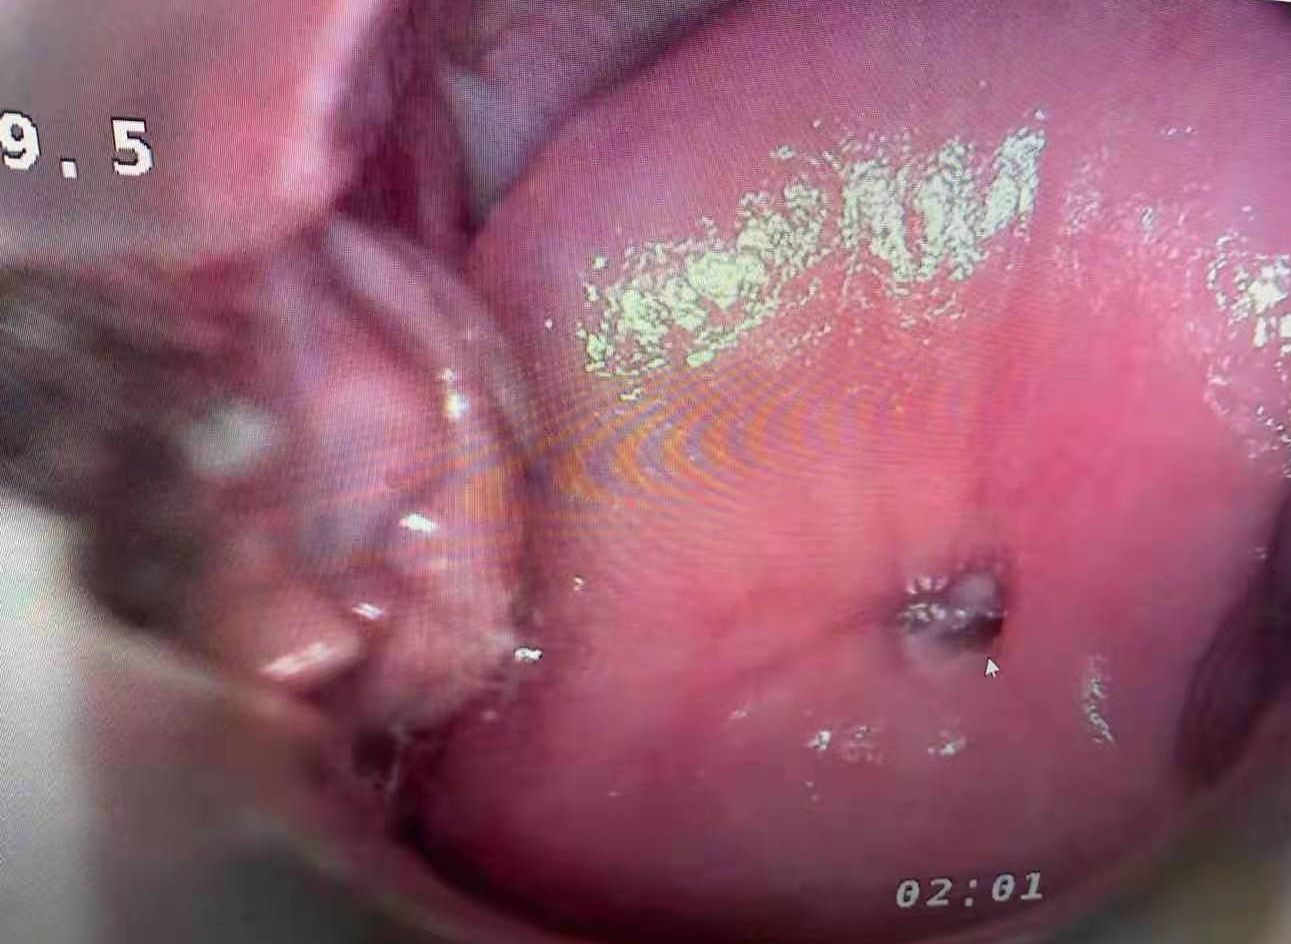

Real cervical diagnosis pictures